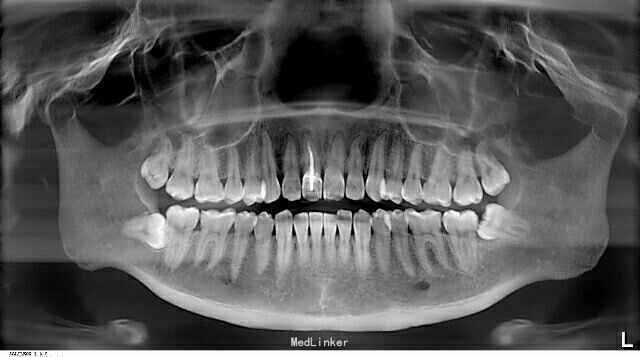

下颌阻生牙拔除

患者,彭某,男,28岁阻生智齿经常发炎,要求拔掉阻生牙处理